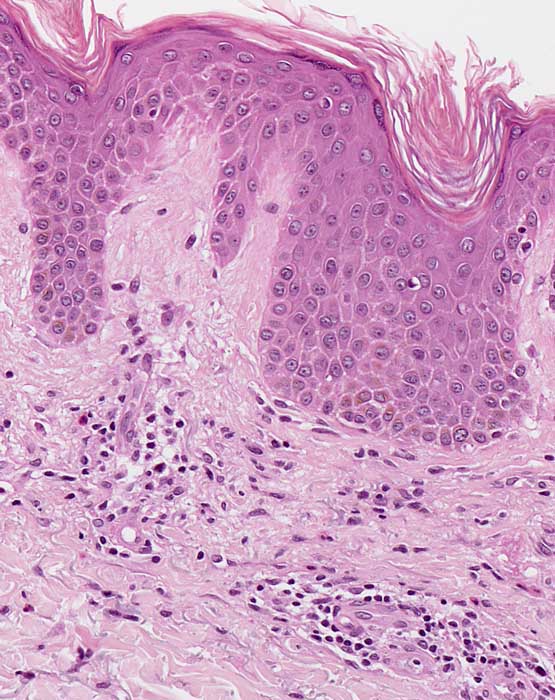

PathoPic ID 7602 - Chronisches Ekzem

Chronisches Ekzem

Entzündung / Reparatur

Haut, Rumpf

Haut

Kompakte Hyper-Orthokeratose. Unregelmässige psoriasiforme Epidermishyperplasie und diskrete Spongiose. Oberflächlich dermales perivaskulär betontes Entzündungsinfiltrat mit Beteiligung einzelner eosinophiler Granulozyten. Geringe Fibrose der papillären Dermis.

Chronische Kontaktdermatitis.

Histologie

200